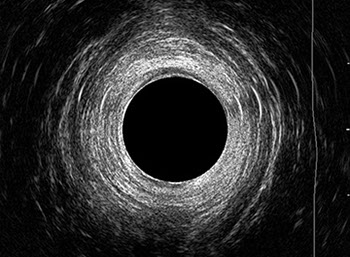

L’ecografia transanale è un esame diagnostico per immagini che consiste nell’introduzione di un trasduttore ad ultrasuoni. Le immagini qualitativamente migliori del canale anale sono ottenute usando un trasduttore rotante, montato in un manipolo rigido, che fornisce un’immagine a 360°. Con le apparecchiature più moderne è anche possibile ottenere immagini tridimensionali.

L’ecografia transanale permette di distinguere la sottomucosa che riveste il canale anale, lo sfintere anale interno, e lo sfintere anale esterno.